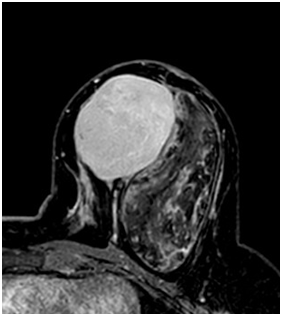

A 47year-old woman with history of a long standing palpable mass on the left breast, which was biopsied on 2006 resulting in hamartoma. She had first degree familiar history of breast cancer with her mother diagnosed younger than 50 \years of age and who later on died of that cause. The patient presented to our office, in June 2016 for progressive growth of her breast tumour. At examination her breasts were fibrous, with a palpable firm and mobile breast mass, not fixed to skin, of 8x6x5cm on the left LIQ, and another large, soft and well defined mass in left LOQ and UOQ of 10x10x5cm, There were no palpable masses in the axilla. On mammography there was a radiolucid well defined breast mass in the left LOQ and UOQ, which was stable in size and shape regarding prior mammogram of twoyears. A new dense, oval and partially defined breast mass was evident in the LIQ (Figure 1). The latter on breast ultrasound corresponded with a hypoechoic and heterogenous nodule with partially defined margins, which measured approximately 7cm. The first lesion was heterogenous and hyperechoic, measured more than 8cm, and was the previously biopsied nodule (Figure 2). She later on underwent a breast MRI that showed a round mass in the LIQ, which was hyperintense in T2, hypointense in T1, had a homogenous enhancement with a plateau curve. In the LOQ there was a well-defined mass, which was heterogenous with fibrous and fatty tissue, and did not enhance with gadolinium (Figure 3). A core biopsy of the two masses was then performed, demonstrating a biphasic fibro-epithelial lesion compatible with a PT at the LIQ, and fibrocystic changes and intraductal hyperplasia without atypia at the LOQ. On August 2016, the patient underwent a partial mastectomy, without incidents, and was sent home on the subsequent day (Figure 4). The definitive biopsy demonstrated that the tumour at the LIQ corresponded to a malignant PT (Figures 5) (Figure 6), and that the LOQ mass was a large breast hamartoma (Figures 7 & Figure 8). Posteriorly, she received 25 radiotherapy fractions, without major adverse effects. She was recently controlled with breast ultrasound and MRI that showed no residual breast lesions.

Figure 3 Preoperative breast MRI (T2 weighted image, T1 weighted image, STIR and gadolinium enhanced high resolution T1WI with fat saturation).